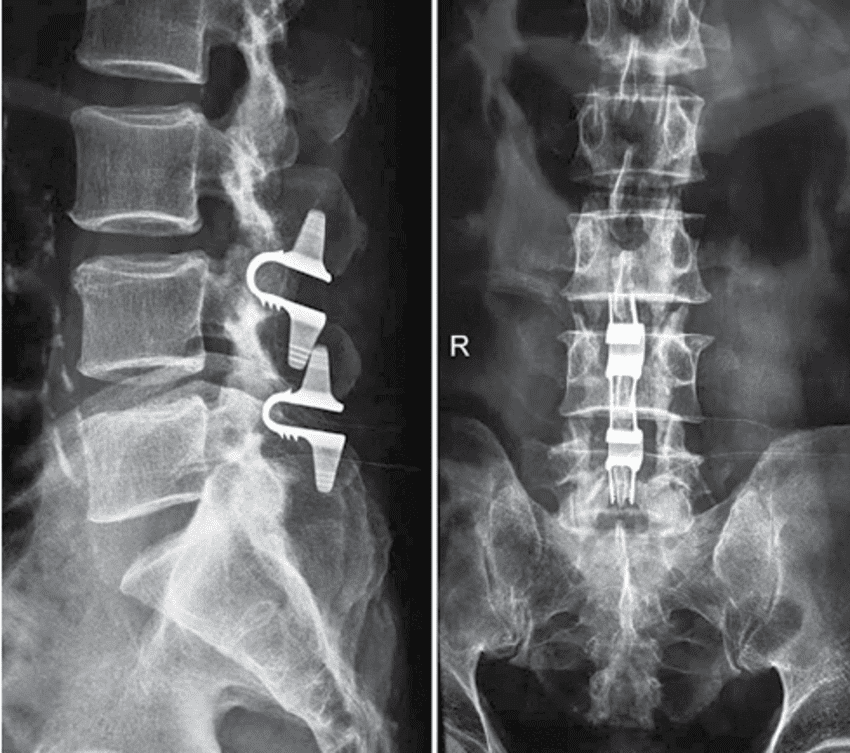

Soy médico especialista en cirugía neurológica y columna vertebral, con la experiencia profesional en el uso de la tecnología más innovadora a nivel mundial, para lograr los mejores resultados en las enfermedades del cerebro y la columna vertebral.

Soy médico especialista en cirugía neurológica y columna vertebral, con la experiencia profesional en el uso de la tecnología más innovadora a nivel mundial.